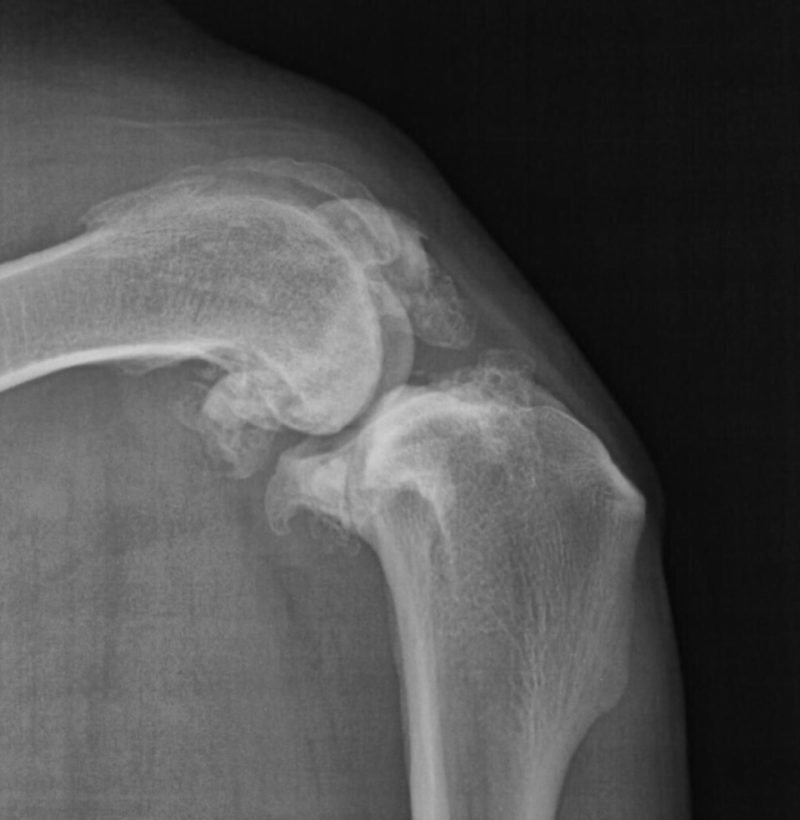

Nichts geht mehr? Urmels neue Menschen ergreifen den letzten Strohhalm. Ende April 2017 wird Urmel von ihrer Pflegerin Fatma nach Schweinfurt gefahren, um sie hier im Tiergesundheitszentrum näher zu untersuchen. Nach einer Gangbildanalyse (die bei einem so schwerfällig und nur mit Unterstützung einer Tragehilfe laufenden Hund natürlich nur eingeschränkt möglich ist) werden nach der anschließenden etwa zweistündigen orthopädischen Untersuchung aller Gelenke noch weitere Röntgenbilder von den Gelenken angefertigt, die in der Türkei nicht untersucht worden sind. Es zeigt sich, dass der Zustand noch schlechter ist als eh schon befürchtet: Urmel hat auch Arthrosen an der Wirbelsäule und weiteren Gelenken. Schließlich werden Urmel insgesamt 62 Berlock-Goldimplantate (das sind kleine spulenförmige Goldimplantate aus Dänemark) implantiert.

Infolge einer Gewichtsverlagerung bei solchen an einem Gelenk schwer gehandicapten Hunden kommt es über die Monate zu Folgeschäden an anderen Gelenken. Diese Schäden können sich bis zu den Zehengelenken ausdehnen. Häufig sehen wir dabei Arthrosen an den Zehengrundgelenken. Nicht selten sind die Sesambeine dieser Zehen frakturiert, durch Überlastung richtiggehend zerbröselt. Gerade solche Schäden aber werden leider zu oft übersehen. Wird eine solche Sesambeinfraktur übersehen, lahmt der Patient trotz aller weiteren Maßnahmen meist weiter. Da nutzt auch die beste Rekonstruktion der Patella am Knie nichts.